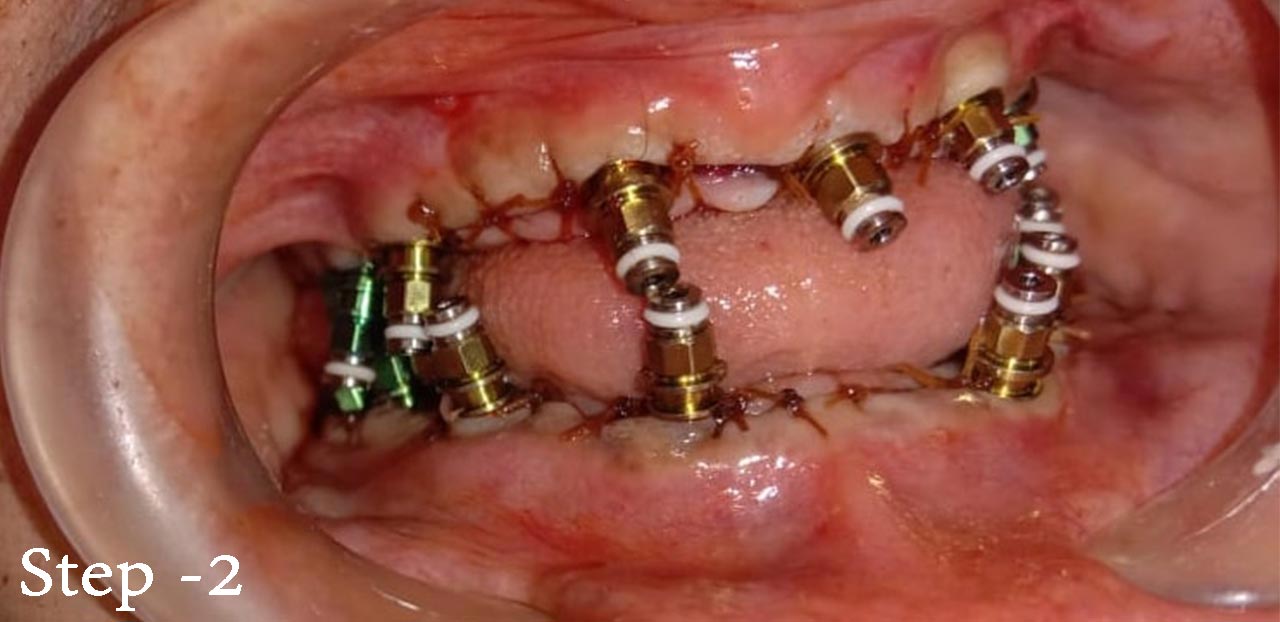

fig 2 - Decayed and damaged teeth removed side by side and implants placed

Step 2 : Root piece removed under LA without pain.